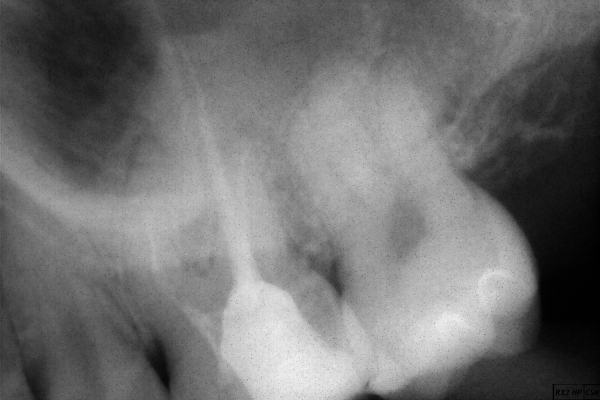

Еще вопрос: есть ли развитие периодонтита на 1 корне?

Конечно есть, обратите внимание на затемнение. Срочно обратитесь к грамотному терапевту, и пломбируйте каналы современными и качественными материалами.